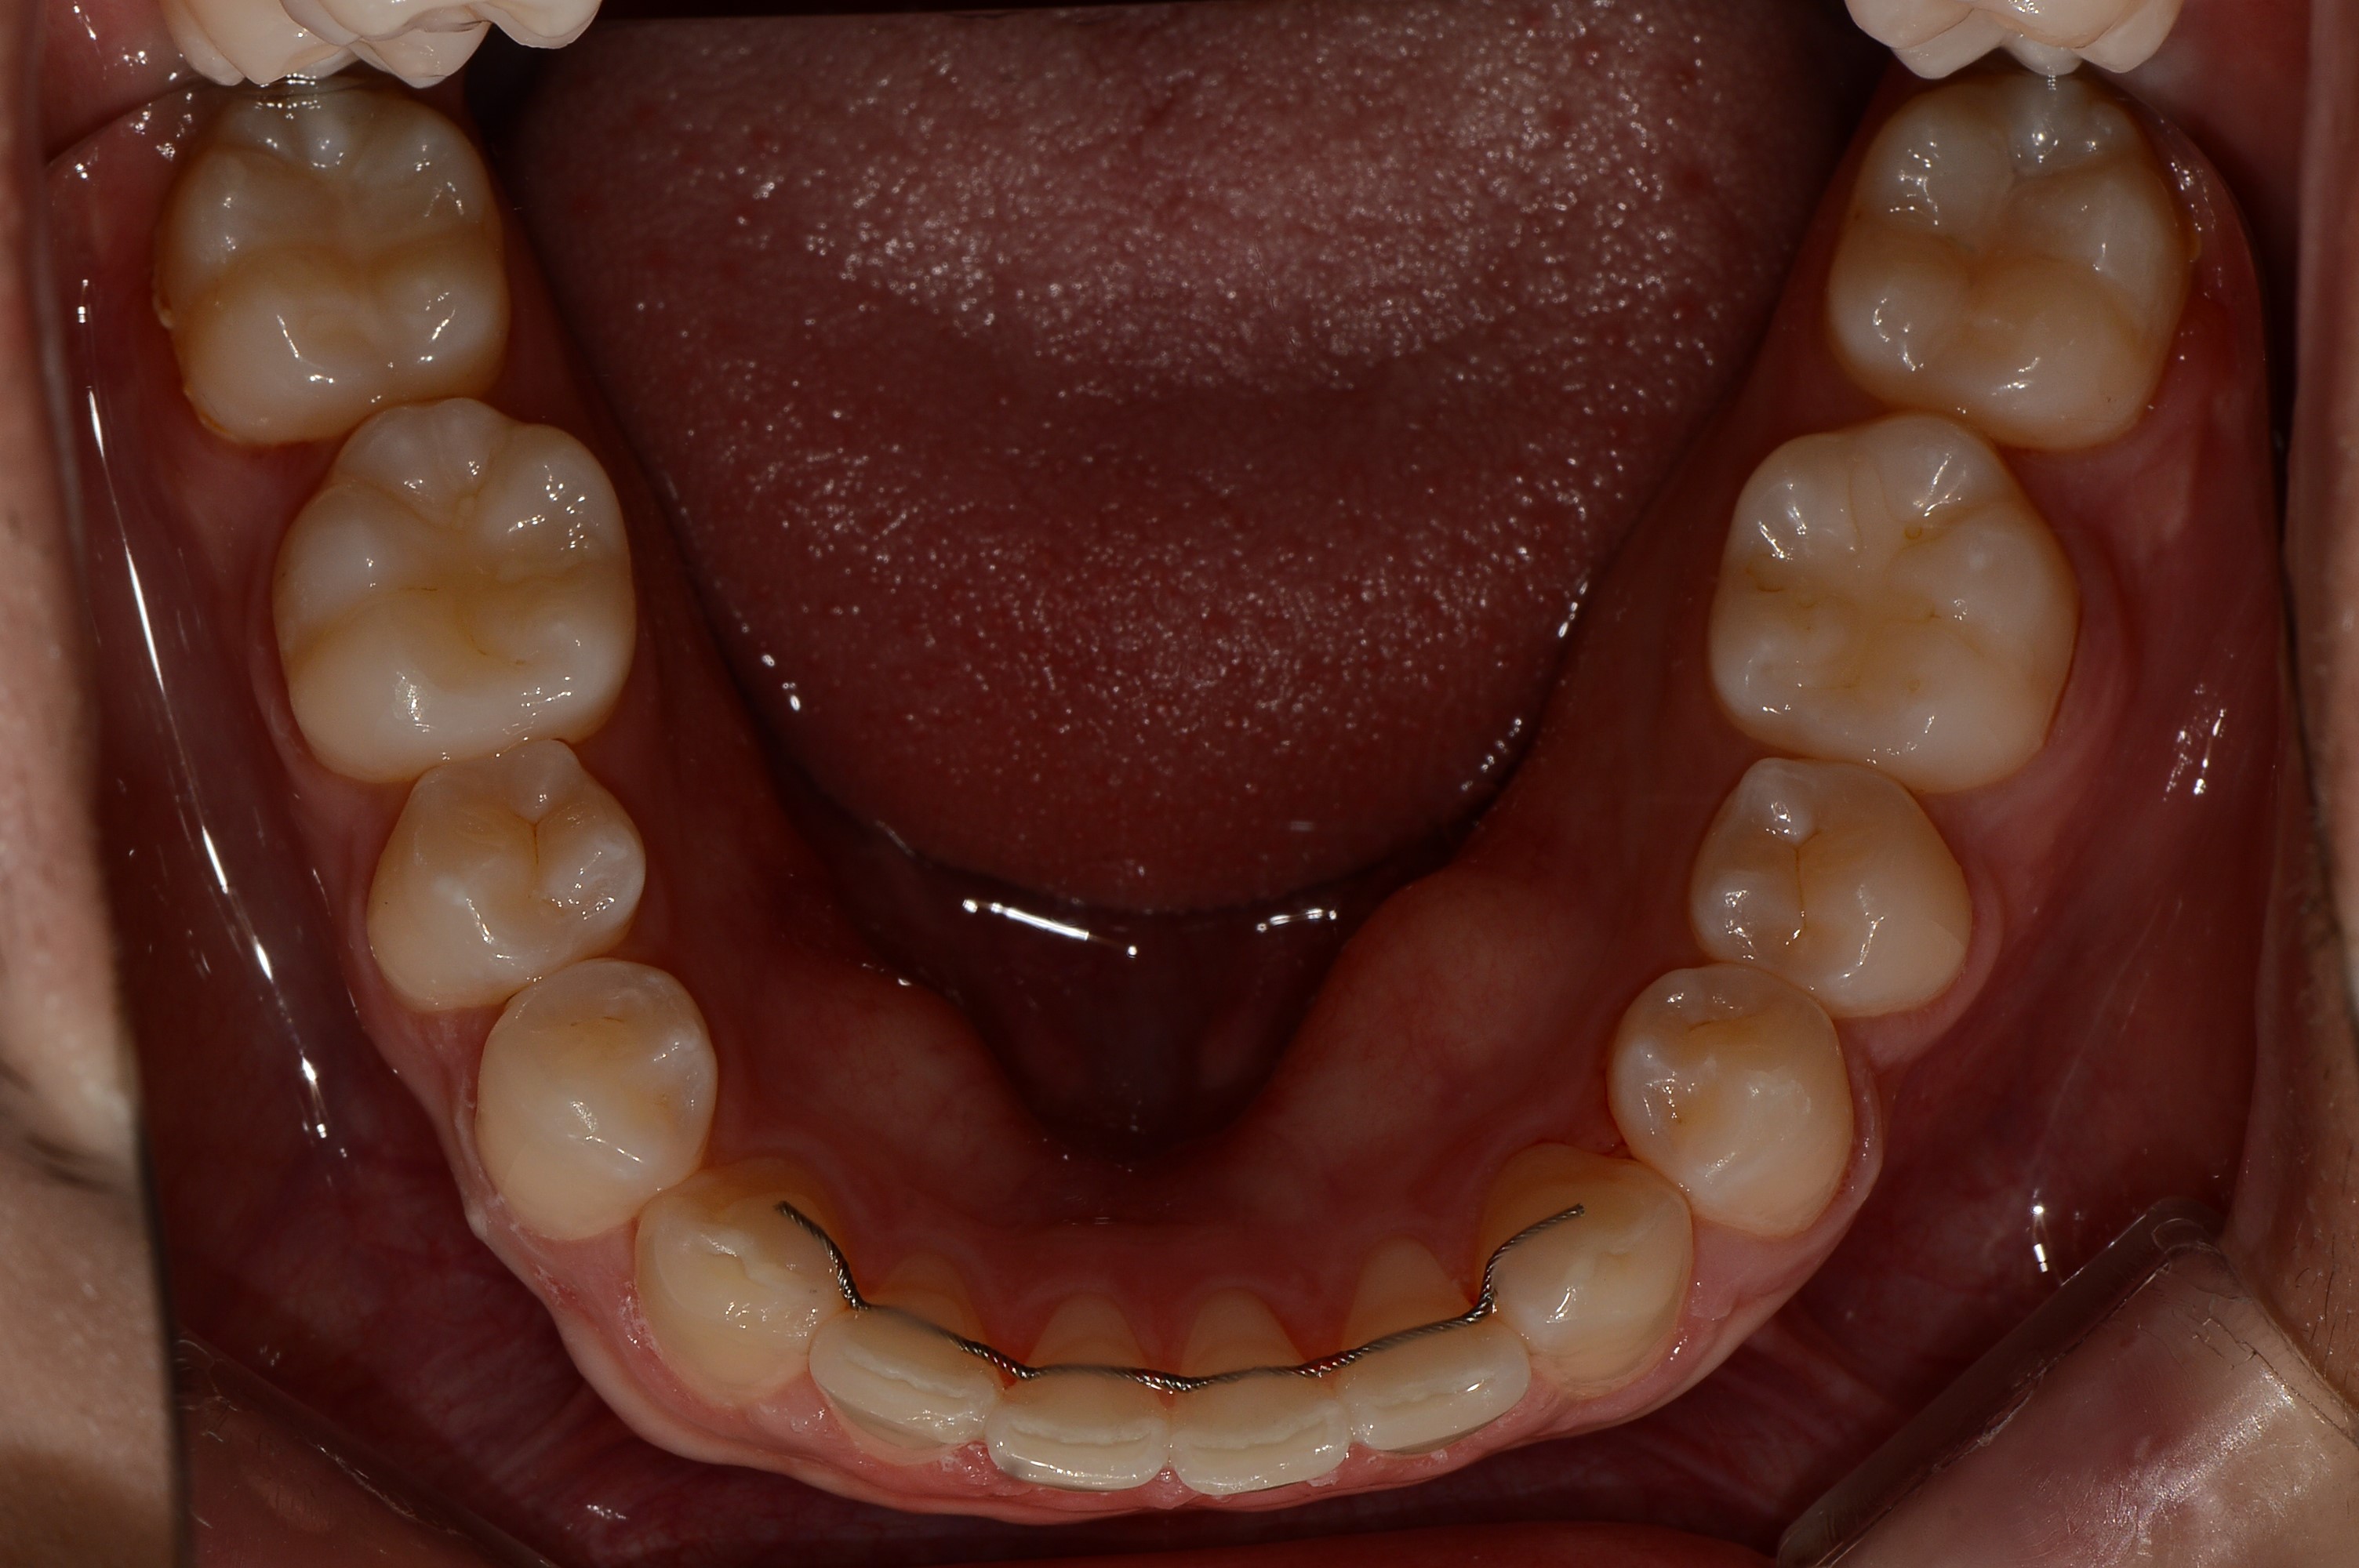

치료 후 사진입니다.